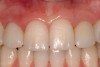

The transitional titanium abutments were left in place for 8 weeks. During this time, the morphologically shaped,.computer-milled abutments supported the interproximal tissue and developed the desired emergence profiles. The.computer-milled abutments were created to a.commodate the adjacent teeth and opposing occlusion, and to aid in the fabrication of the final porcelain-fused-to-metal (PFM) restorations (Figure 20A and Figure 20B). The final crowns were delivered 4 months after implant placement. The radiograph of the emergence profile confirmed the seamless fit of the abutment-implant-crown interfaces (Figure 21). The final restorations were esthetic, functional, and met the needs of the patient (Figure 22A). The re-establishment of the interdental papilla.completed the careful transformation of the flat alveolar crestal tissue into a proper emergence of the clinical PFM crowns, indistinguishable from the surrounding dentition (Figure 22B).

Figure 22a  The final restorations are indistinguishable from the surrounding dentition, demonstrating good emergence and re-creation of the interdental papillae.

Figure 22a

Figure 22b  The final restorations are indistinguishable from the surrounding dentition, demonstrating good emergence and re-creation of the interdental papillae.

Figure 22b